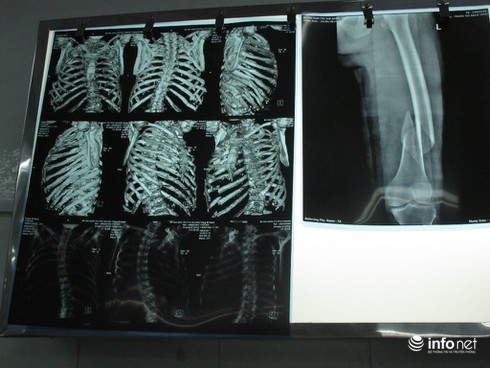

Xương sườn và xương đùi bệnh nhân bị gãy. Hình ảnh chụp bằng phim X-quang |

Qua kiểm tra, xét nghiệm cận lâm sàng cho thấy, bệnh nhân bị gãy 8 xương sườn bên phải, gãy xương đùi phải, một bên phổi bị tràn dịch khiến bệnh nhân không thở được. Ngay lập tức, bệnh nhân được đưa vào phòng mổ cấp cứu để dẫn lưu máu đọng trong phổi, cố định phần xương gãy.